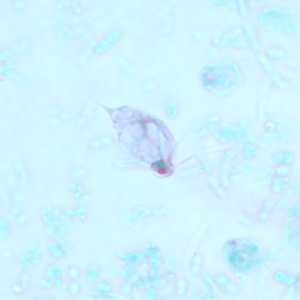

Within a week of returning from a conference in Mexico, a 28-year-old woman presented to her primary care physician with cramps, abdominal pain, gas and diarrhea. A routine Ova and Parasite (O&P) examination was performed on stool specimens.

May - 2008 - Case #227